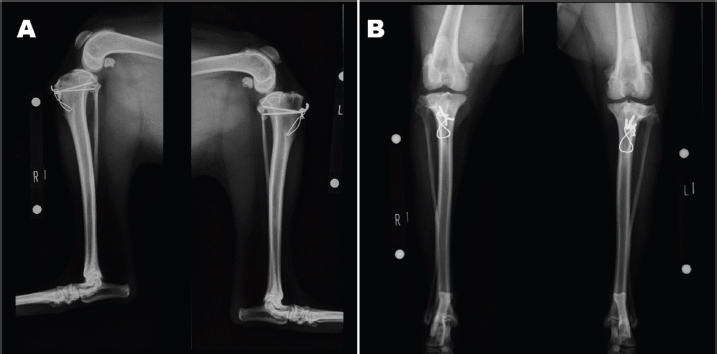

An 11-month-old intact male Siberian Husky was referred to us with the main complication reported as bilateral hind lameness and LPL, diagnosed by a family doctor. His posture showed an X-linked knee. Physiological examination showed bilateral patellar luxation with grade 4 and negative for cranial drawer sign and tibial compression test. The radiograph showed severe bilateral LPL without changes in the hip joint (Figs. 1A-B). His quadriceps (Q) angle showed right=43.37°and left=32.15°. Diazepam 0.1 mg/kg, ketamine 0.5 mg/kg, and fentanyl 5 μg/kg (intravenous), atropine 0.05 mg/kg (intramuscular), and meloxicam 0.2 mg/kg (subcutaneous) were administered as the premedication. After an induction of propofol 6 mg/kg, ropivacaine 0.22 mg/kg was used for epidural anesthesia. Under general anesthesia, the patient was immobilized in the supine position. Surgical techniques included bilateral block trochleoplasty, tibial tuberosity with tension band wiring using Kirschner wire, modified capsules (release of the lateral capsule and suturing of vastus medialis, plication), and the modified MPFL. The modified MPFL was used with the Cruciate Needle (medium, 40 lb) 40# suture (monofilament nylon) single strand (SECUROS, MA), suturing from the lateral aspect of the patella periosteum to the medial sesamoid bone (Figs. 2A-B). The postoperative radiograph is shown in Figures 3A-B. The patient has shown no luxation over 1 year after the operation.

Fig. 3. Postoperative radiograph.